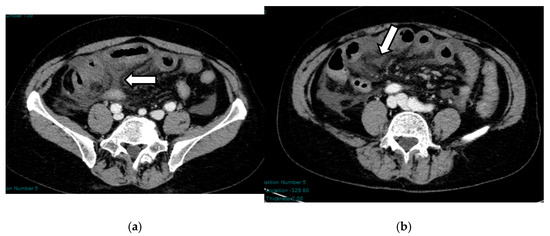

Acute mesenteric ischemia (AMI) is a clinical condition caused by vascular insufficiency, resulting in intestinal damage. Is often underestimated, if not driven by clinical suspicion, due to the non-specific clinical symptoms (usually represented by acute abdominal pain) and the absence of reliable markers, which results in a poor prognosis and high mortality. We can identify three main forms of AMI: arterial, venous, and non-occlusive. Arterial AMI is the most frequent form, caused by occlusion of the superior mesenteric artery or one of its branches. Venous AMI is the least frequent, caused by thrombosis of the superior mesenteric vein or its branches. Non-occlusive AMI is due to a state of hypovolemia, which is frequent in patients who have undergone surgery. Given the difficulty of diagnosis based on the clinic alone, the radiologist plays a central role in identifying radiological signs of intestinal ischemia and in avoiding misdiagnosis. The radiologist’s role is mainly to identify factors predictive of necrosis, which allow us to stratify patients and direct them towards the proper management. The aim of this review is to provide indications for an adequate CT protocol, including an unenhanced phase, an arterial phase, and a venous phase, as well as to underline the features to investigate in the different forms of AMI, in order to increase the diagnostic capacity in this challenging disease. Full article

Figure 1